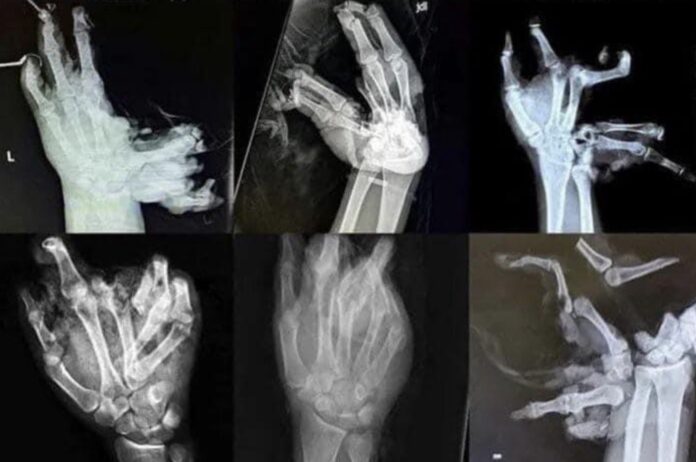

These precautions are crucial for preventing injuries, as shown in the graphic images shared by the coroner’s office depicting severe hand injuries caused by fireworks. The office stresses the importance of celebrating responsibly and prioritizing safety to ensure an injury-free holiday.